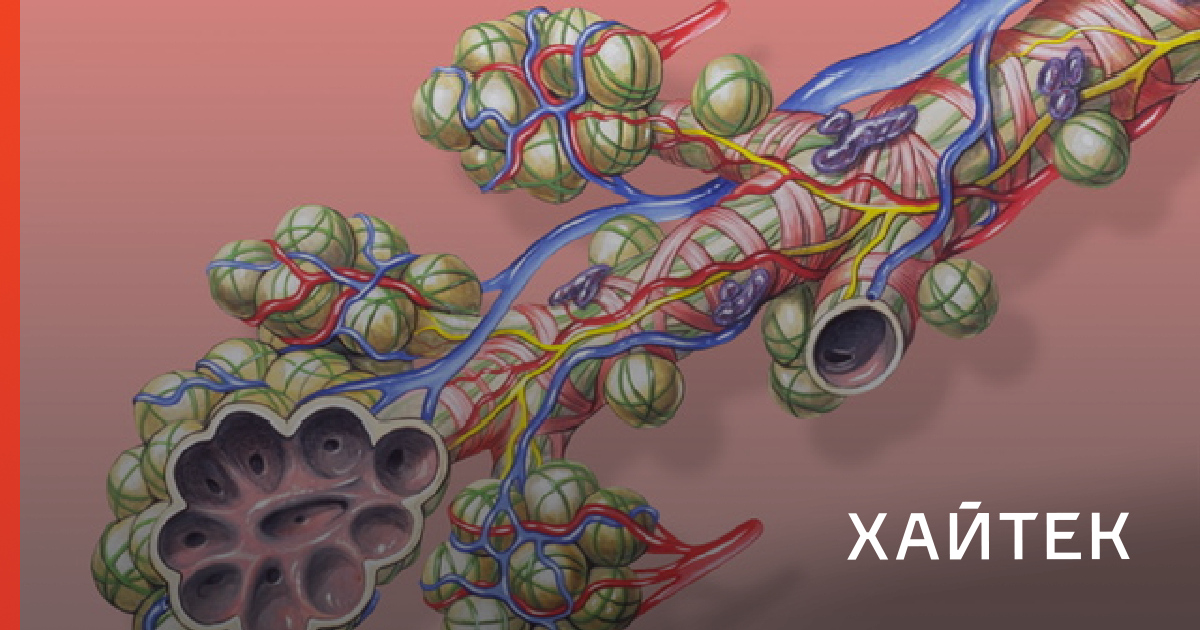

Роль легких в метаболических процессах